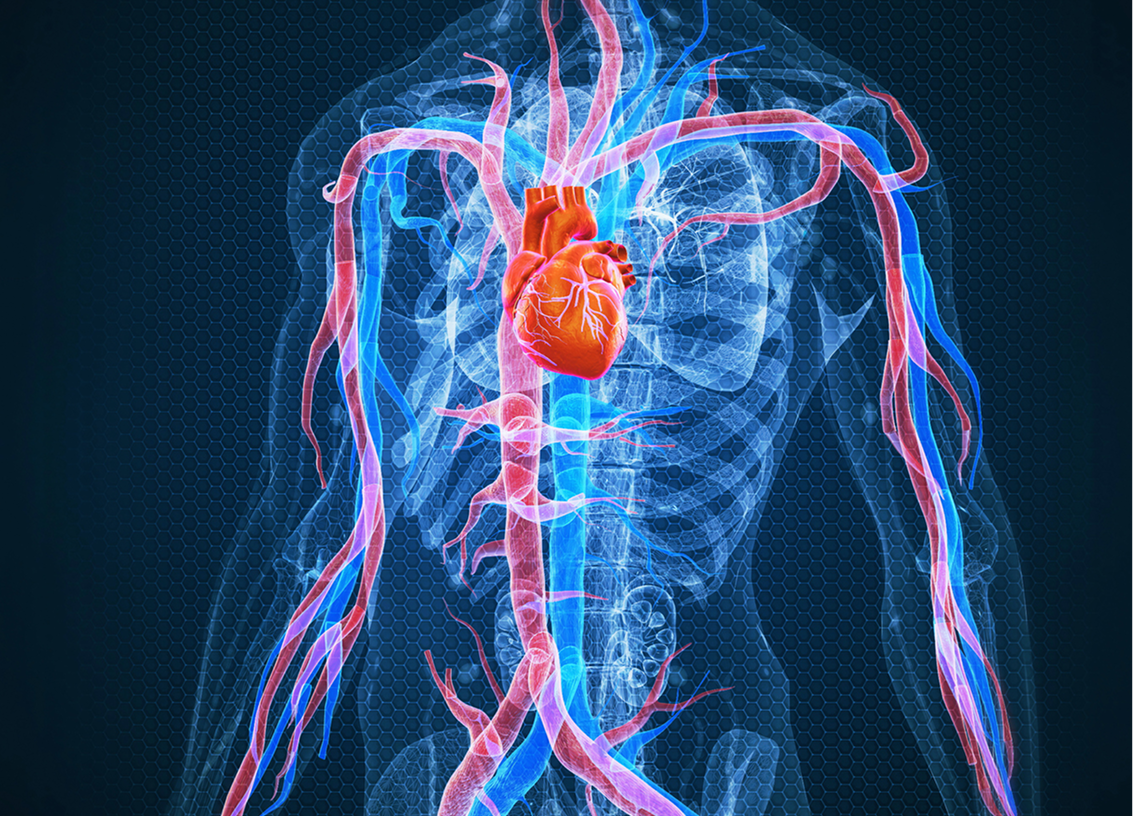

Si vous ne dormez pas suffisamment, votre corps n’a pas le temps nécessaire pour réguler les différentes fonctions et organes, notamment le cœur, les vaisseaux sanguins et la santé du système circulatoire en général. Voici certains des effets à long terme de l’insomnie :

Lors d’une nuit de sommeil normale et saine, la tension artérielle diminue. Cette « chute nocturne » est importante pour la santé du cœur, et un manque de sommeil peut l’entraver. Cette situation peut augmenter le risque d’hypertension (c’est-à-dire une tension artérielle élevée). L’hypertension exerce une pression supplémentaire sur le cœur et les vaisseaux sanguins, en plus d’être associée à des risques plus élevés de maladies du cœur et d’accidents vasculaires cérébraux.

Risque accru de maladies du cœur

Des études ont montré que les personnes souffrant d’insomnie chronique sont plus susceptibles de développer des maladies du cœur. Le manque de sommeil peut entraîner une inflammation des artères et l’accumulation de plaques. Avec le temps, ce phénomène rétrécit les artères, rendant la circulation sanguine plus difficile et augmentant le risque de maladies du cœur, y compris d’infarctus.